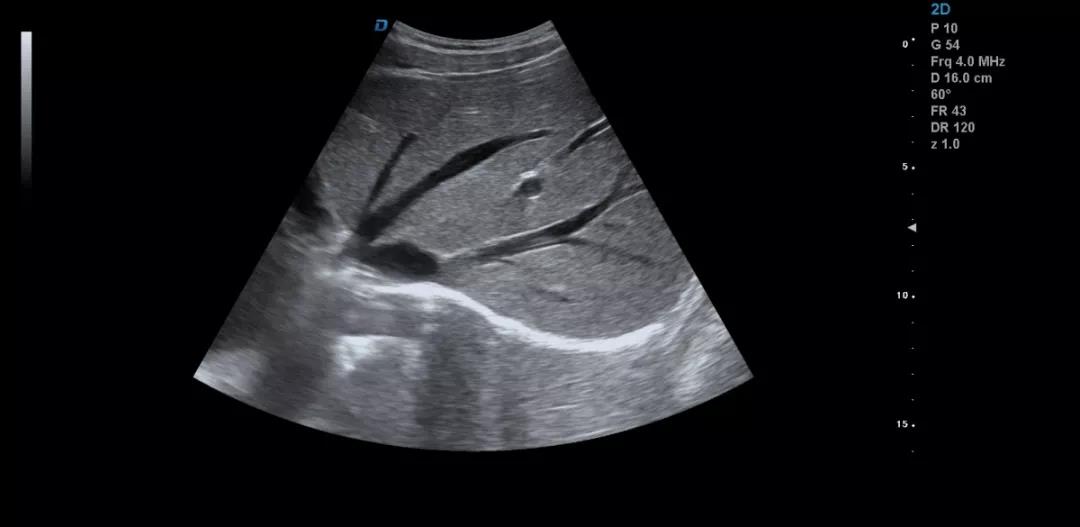

彩超機肝臟超聲的檢查方法詳解

彩超機是每個醫院常見的診斷設備,很多人都不陌生。可能大家認為彩超機檢查醫生很輕松,其實不然,彩超檢查醫生也是需要精湛的操作技術,專業的判斷才可以的。下面小編和大家一起來看下利用彩超機檢查肝臟超聲的方法。

彩超機檢查肝臟超聲方法

彩超檢查不同于其他的影像學檢查方法,彩超檢查的結果與操作者的技術、經驗、手法、檢查細致程度等很多因素密切相關。

眾所周知,肝臟有很多檢查死角,成為超聲檢查的盲區,如肺和骨所掩蓋處,肝右前上段及右后上段的膈頂部,左外葉外側角區,沿肝臟表面的肋骨下區等等部位,只有極其細致的檢查配上精巧的手法才能盡可能的顯示清楚這些部位。

掃查肝臟時要配合患者的呼吸運動,采取你動我靜,你靜我動的掃查方法,并最大限度的側動探頭,最大角度的顯示肝臟。

發現肝臟病變時要多切面多角度掃查,可以了解病變的解剖位置并排除假陽性。